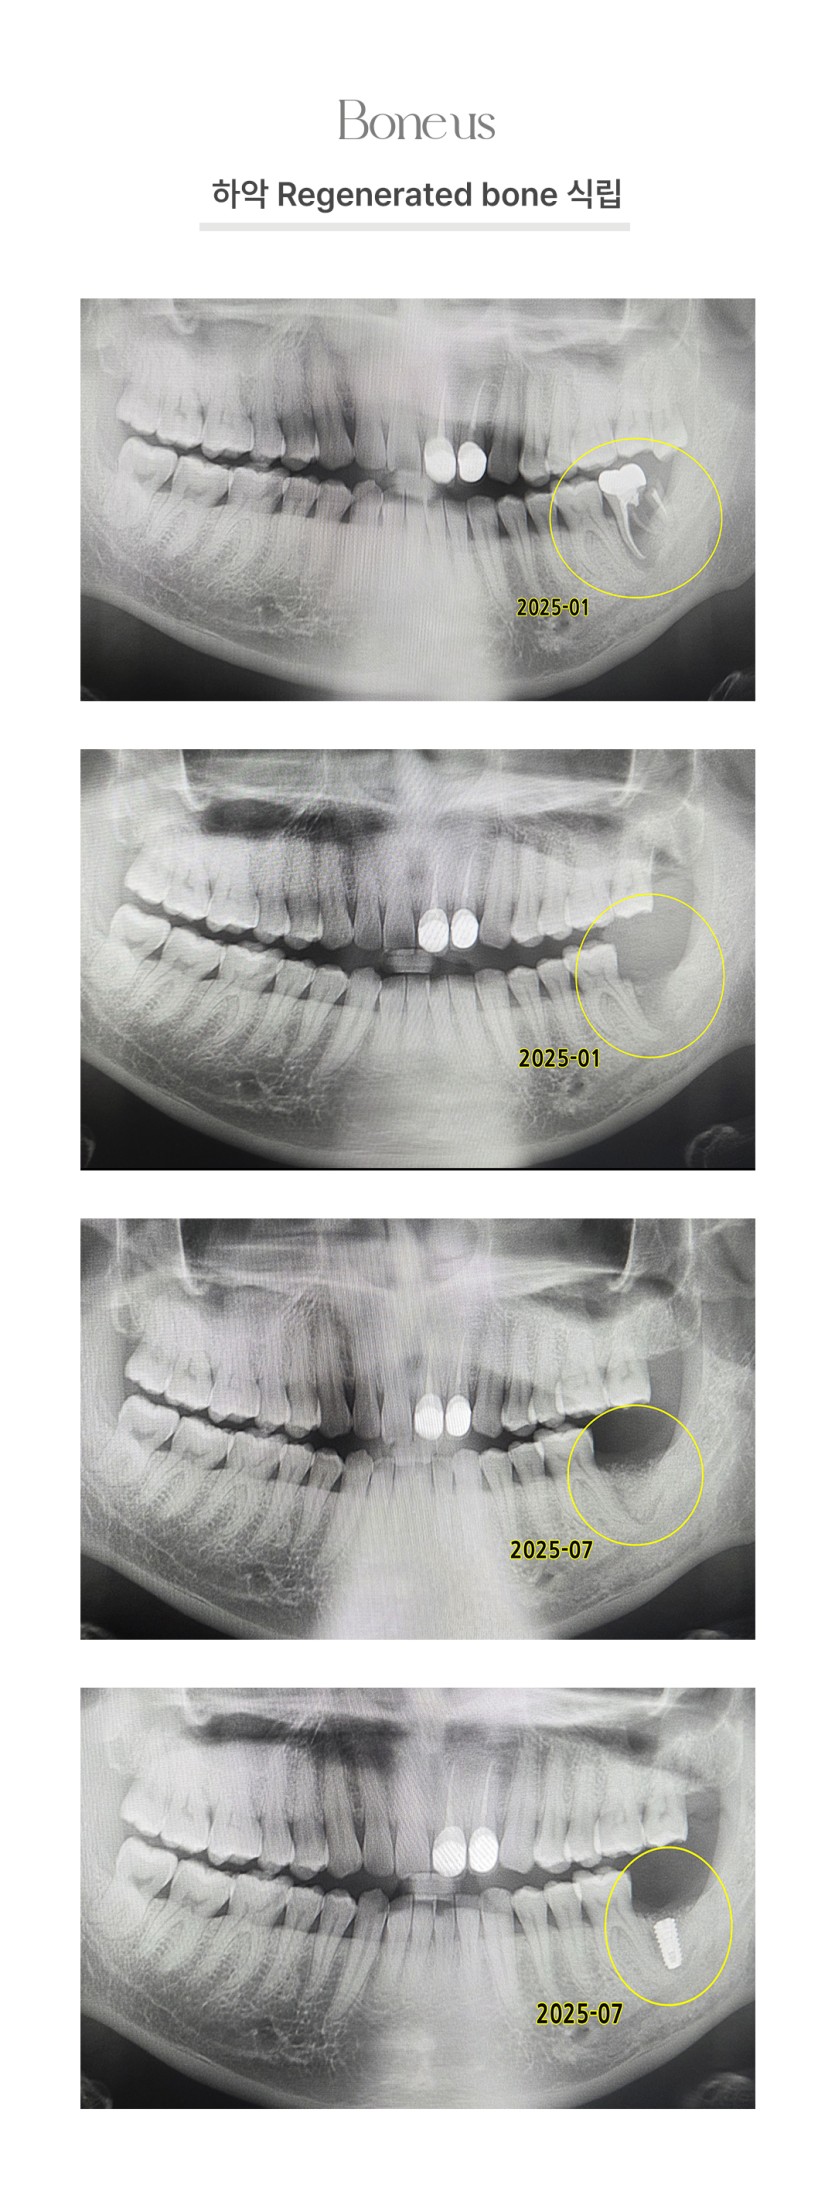

하악 Regenerated bone 식립 2

하악 Regenerated bone 식립 1